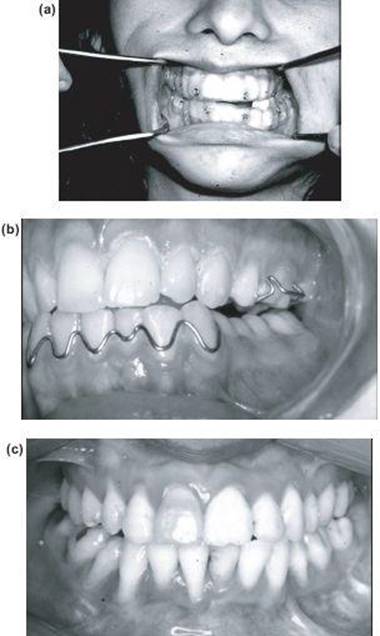

18. A contralateral coronoidectomy or otomy is essential to give maximum opening. This is done intraorally after stretching the mouth open with a Featherstone or similar self-retaining gag. Two blade (Lacs) retractors are required and are pressed, one on each side of the anterior border of the ascending ramus. Incise downwards between them through the mucosa and muscle to the bone. Elevate the periosteum and muscle layer on both sides of the ascending ramus and insert the blade retractor (Lacs) in each pocket, then using the forked Langenbeck retractor, the coronoid is exposed and grasped with curved Kocher forceps and divided obliquely at its base with a bur. The last remaining bony bridge which is the anterior rim of the sigmoid notch is fractured with an osteotome inserted in the bur cut and twisted. As the coronoid process is elongated its removal can be difficult and is probably unnecessary. The stretched opening of the mouth can now with effort be doubled (Figures 13.10a to 13.10c).

Figure 13.10 (a) Opening after resection of fused condylar head and coronoidectomy. (b) Intraoral contralateral coronoidotomy and (c) significant increase in mouth opening.